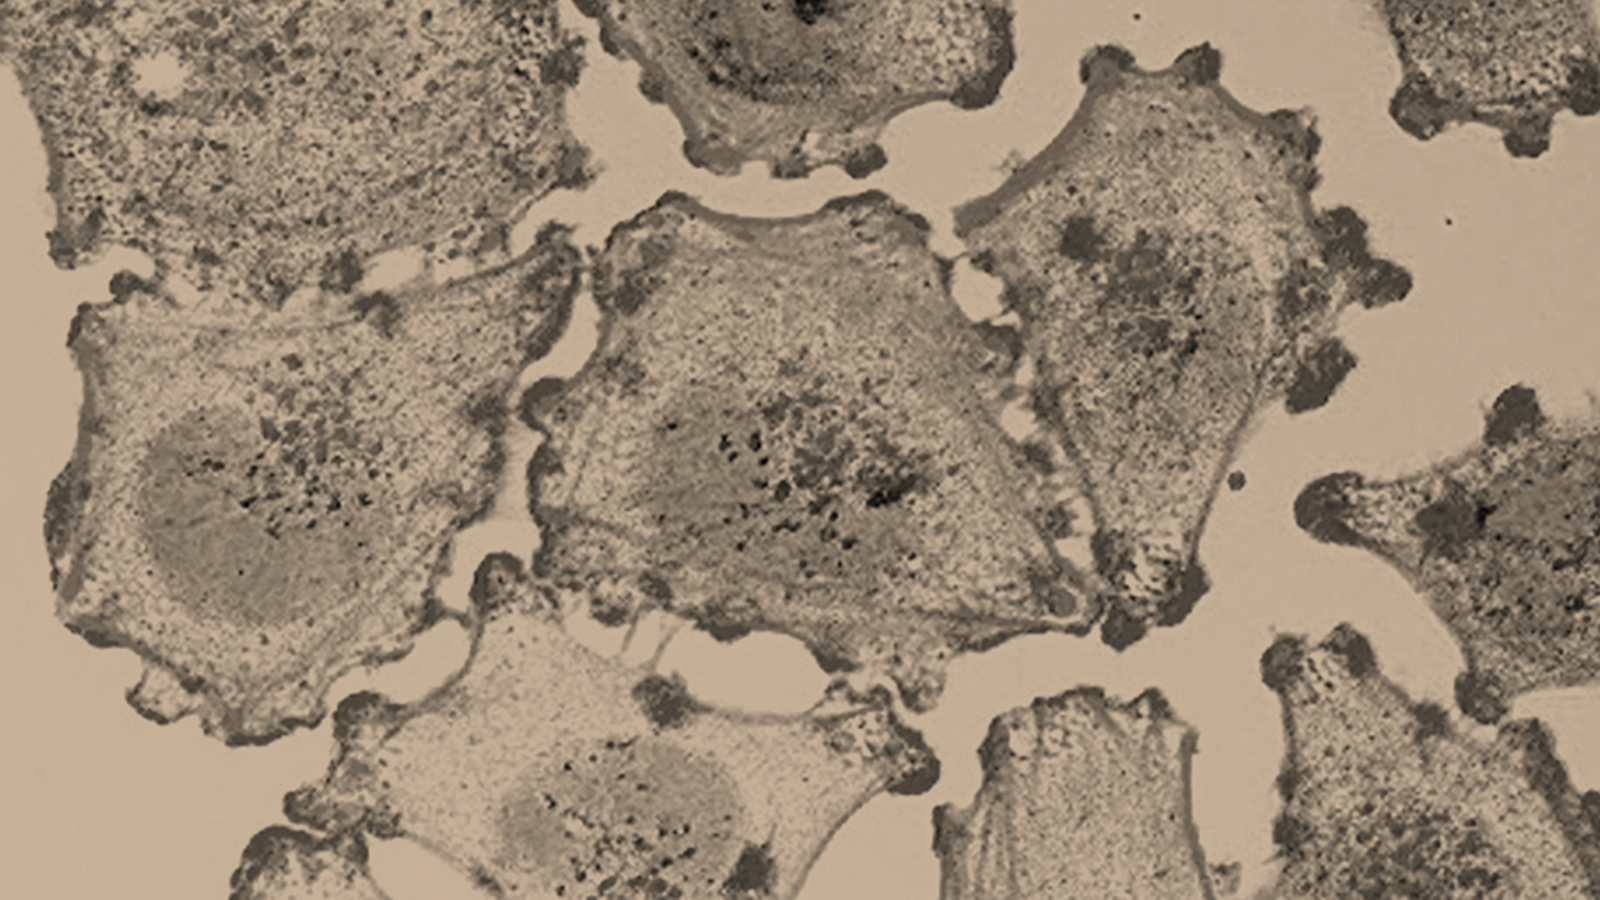

«Càncer», una paraula tabú envoltada de mites, metàfores i eufemismes. Una malaltia que ens ha acompanyat durant tota la història però que hem començat a entendre d’unes dècades ençà.